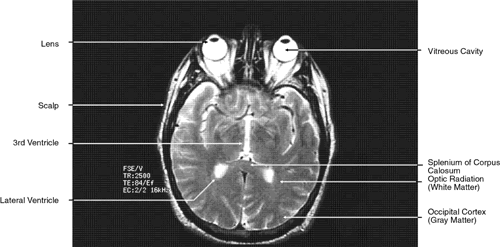

T2-weighted images can be produced at the same time as proton density images. In this case both the TR and TE are prolonged. By allowing all tissues to relax maximally, the most intense signal will be produced by the tissue with the longest T2 (that is, the tissue that remains coherent the longest). A particular tissue's T2, which typically ranges between 25 and 150 msec, is usually much shorter than its T1. To obtain a T2-weighted image, both the TR (>2,000 msec) and the TE (50 to 150 msec) are long (Fig. 9). In such cases, vitreous and cerebrospinal fluid give the most intense images and fat, white and gray matter, bone, and air give the least intense images.

Fig. 9. Axial T1-weighted magnetic resonance imaging through midglobe.

The globe is shown in Figure 12. The orbit and periorbital structures are shown in Figures 13 through 16, and the optic canal is shown in Figures 17 through 26. The cavernous sinus and optic chiasm are shown in Figures 27 and 28, and the posterior visual pathway and cranial nerves are shown in Figures 29 through 33.